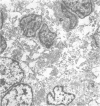

Type I mucopolysaccharidosis was diagnosed in a fetus by assay of the glycosaminoglycans of the amniotic liquor. Results are presented of biochemical and ultrastructural studies on the 18-week abortus. The evidence suggests that the liver is more severely affected than the central nervous system at this stage of gestation, and this finding agrees with the recent demonstration of the underlying enzyme defect of this disorder, with the corollary that many biochemical abnormalities previously noted in gargoylism must be pleiotropic effects of the mutant genotype.